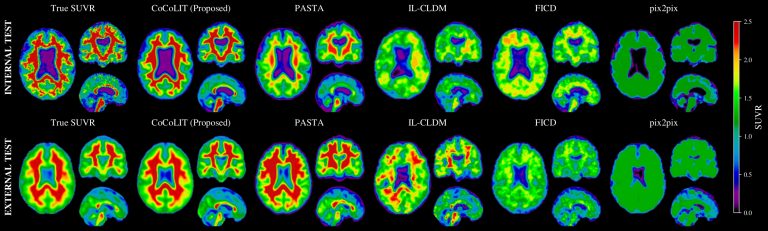

Il progetto CoCoLIT rappresenta una svolta nell’ambito della diagnostica precoce dell’Alzheimer: nasce dall’esigenza di superare i limiti delle scansioni PET…